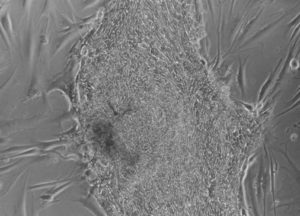

I am a scientist at the University of Manchester and I work several different projects. I am trying new and exciting ways to create Human Embryonic Stem Cells that could possibly be used to help treat diseases like Parkinson’s and diabetes, as well as helping patients with spinal cord injuries (like Superman)

A lot of my time is spent in a room we call “Tissue Culture” which is where we grow cells and embryos in incubators.

The cells and embryos are rather fussy and demanding so we need to keep them at certain temperatures, with a particular amount of oxygen and carbon dioxide. They also have to be kept super clean and free of any infections which is why we keep them in a special room!